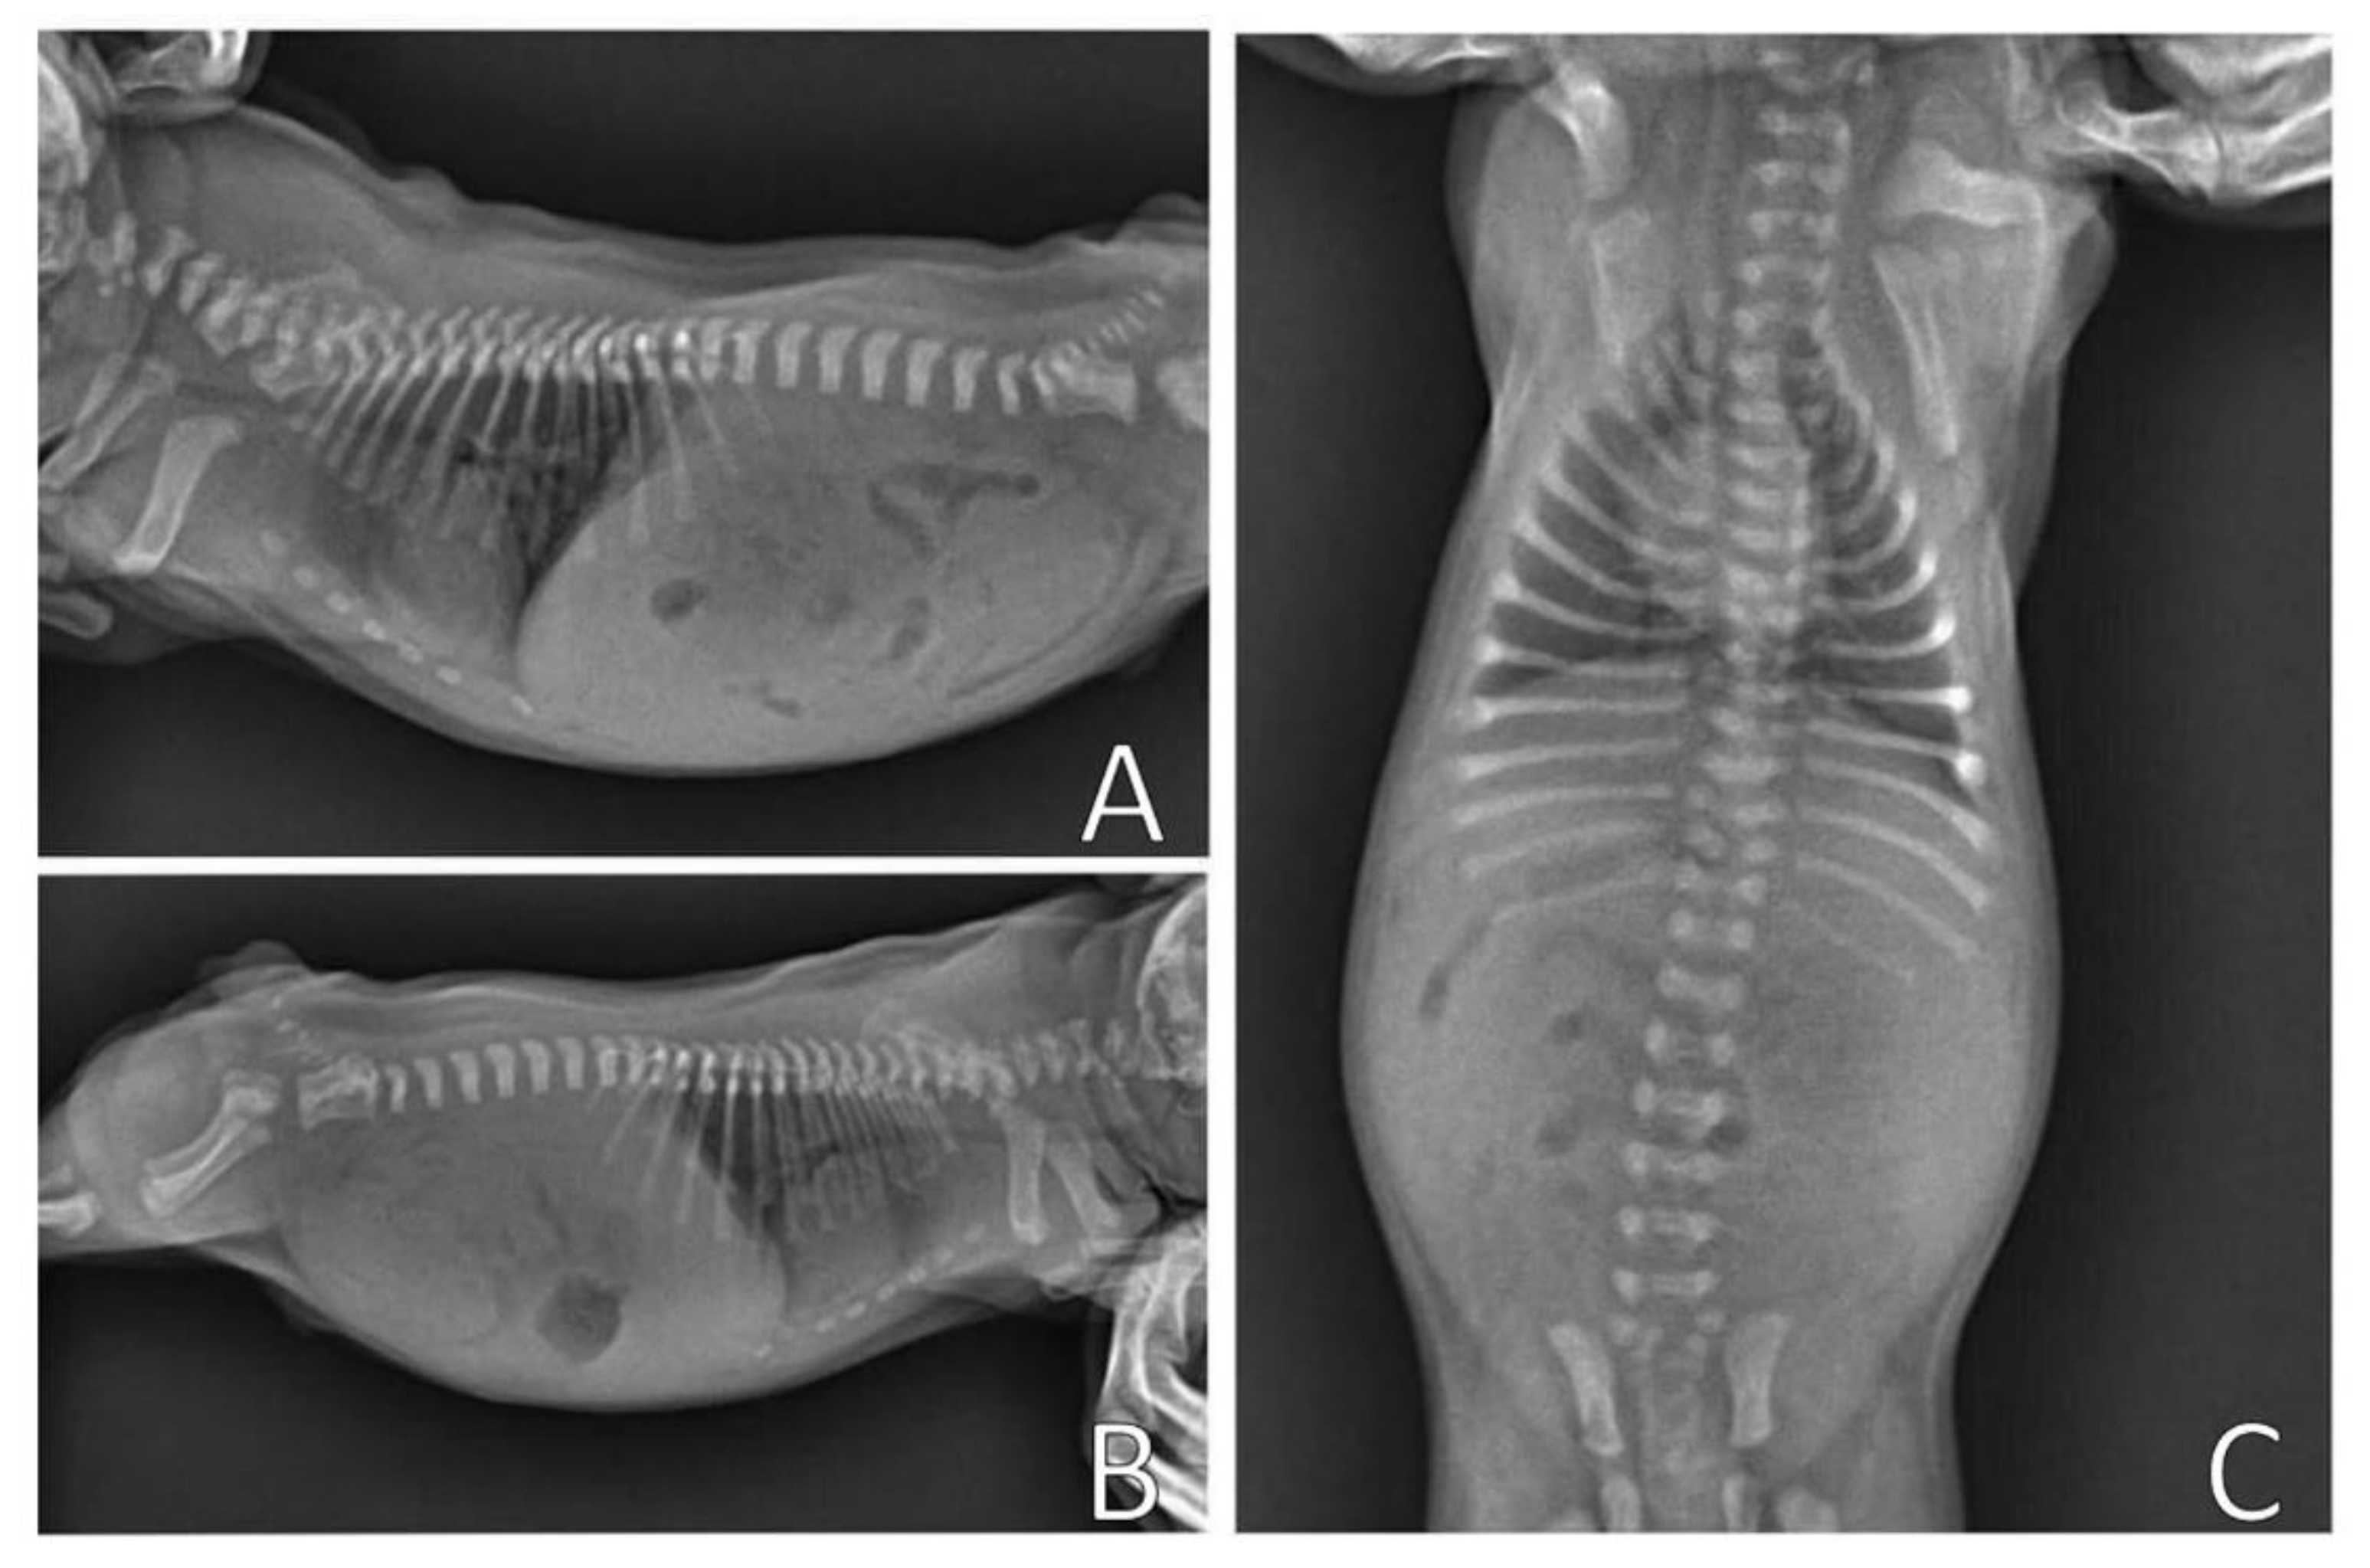

Complementary tests, hemogram and chest X-ray, were performed. Blood (0.4 mL) from the jugular vein was collected for the hemogram, which was within the reference standards for age. The chest X-ray (Figure 11) was performed in the right lateral and ventrodorsal positions, observing a ventrodorsal deviation of the sternum and diagnosing pectus excavatum. The frontosagittal and vertebral indices corresponded to 1.7 cm (≤2 cm) and 10 cm (>9 cm), respectively, classifying the pectus as mild grade. In addition, a rounded cardiac silhouette (globose aspect) and right cardiac deviation were observed.

Figure 11.

Chest X-ray. (A) Right lateral position, demonstrating ventrodorsal deviation of the sternum bone (arrow). (B) Ventrodorsal position, demonstrating rounded cardiac silhouette and right cardiac deviation.